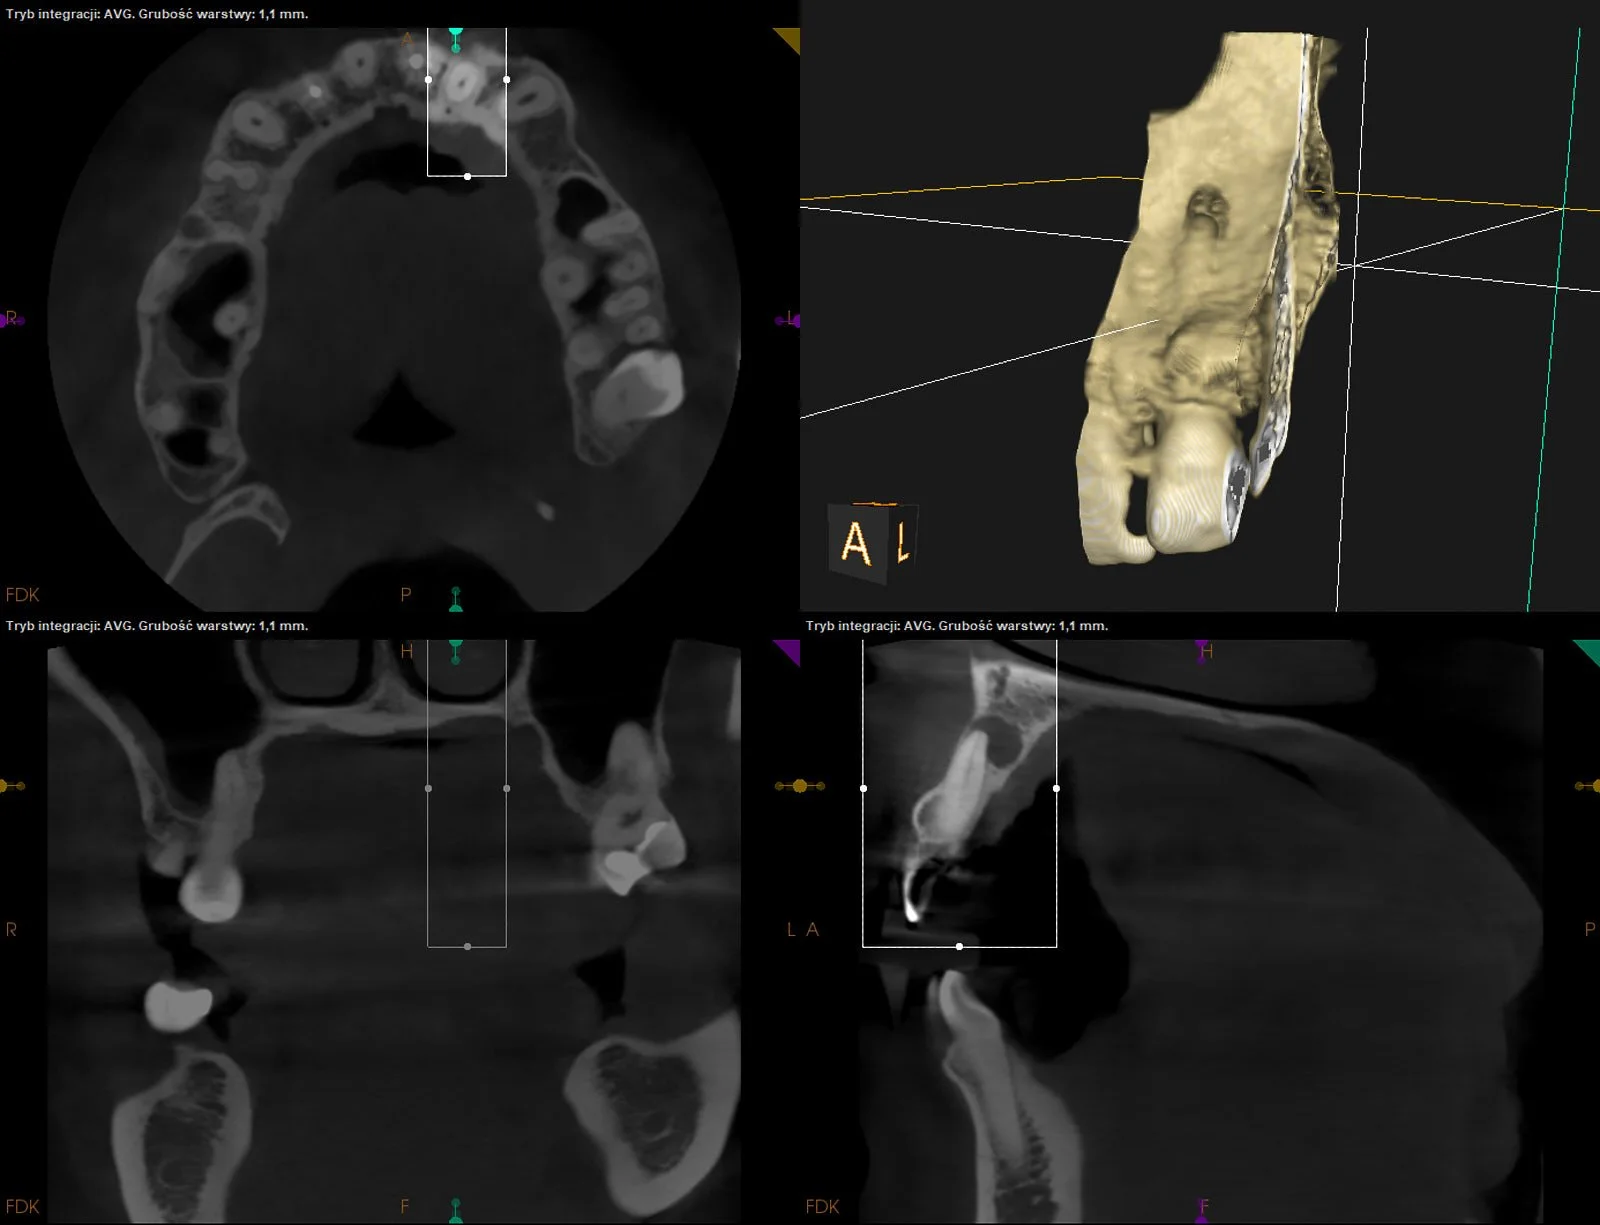

CASE STUDY X

Leczenie kanałowe d.36 z resorpcją wewnętrzną w kanale mezjalnym.